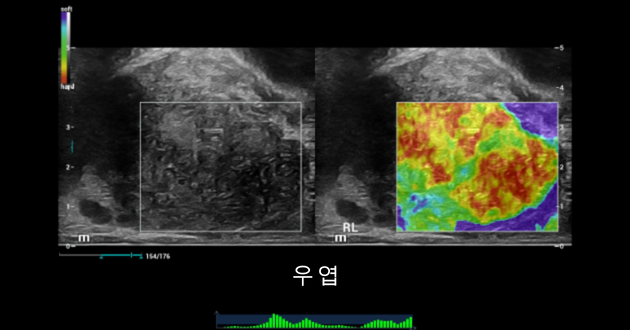

??? ??? ????? ?? ?? ??-?? ??? ???? ???? ???????. ????? ?? ??? ?? ?? 2?? ??? ???? ???, ???? ???? ?????, ???? ????? ????? ??? ?? ? ?????. ???? ???????(NTE: Natural Touch Elastography)? 2D ?? ?? ???(STE: Sound Touch Elastography)? ??? ??????? ??? ?? ??? ????? ?? ???????.

NTE ŌĆō ???? ???????:

??? ?? ???(SWE)? ??? 34kPa, ??? 115kPa? ?? ??(??6). ?? ??? SWE? ???? ? ???? ? ??.(?? = 19 kPa, ?? = 36 kPa). (??7) ????? ??? ????(PZ)?? ???? ?? ???? ???. ????(TZ)? ??? ???? ?? ????(PZ)?? ? ???. ????(TZ)? ????(PZ)? ??? ???.

- NTE? ??? 2D ????? ??? ??? ??? ?? ??? ??? ???????. ??? ???? ?????? ?? ????? ?? ??? ??? ??? ???? ?? ??? ???????.